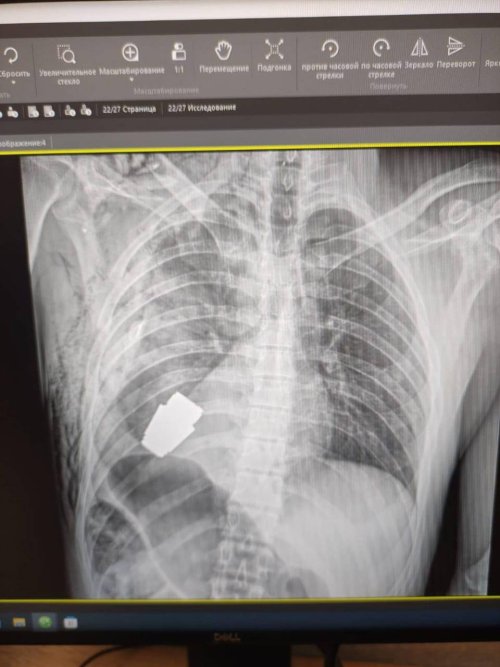

Ukrayna'da bir askerin kalbine yakın bölgesinde VOG el bombası tespit edilmesinin ardından gerçekleştirilen ameliyat sonucu patlayıcı başarılı bir şekilde çıkarıldı.

Ukrayna'da bir askerin kalbine yakın bölgesinde patlamamış VOG el bombası tespit edildi. Bombanın her an patlayabilme ihtimali olduğu için Ukrayna Silahlı Kuvvetlerinin en deneyimli cerrahlarından biri olan Andrii Verba tarafından acil bir operasyon gerçekleştirildi. Ukrayna Savunma Bakanı Yardımcısı Hanna Maliar, cerrahi müdahalenin başarılı olduğunu ve askerin tedavi altına alındığını söyledi.